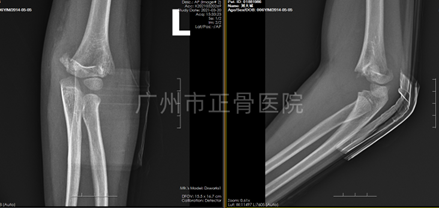

X线片示:左肱骨髁上骨折,骨折远端向后、向尺侧移位,软组织明显肿胀。

▲复位前,骨折端明显移位

▲复位后,骨折端对位对线明显改善